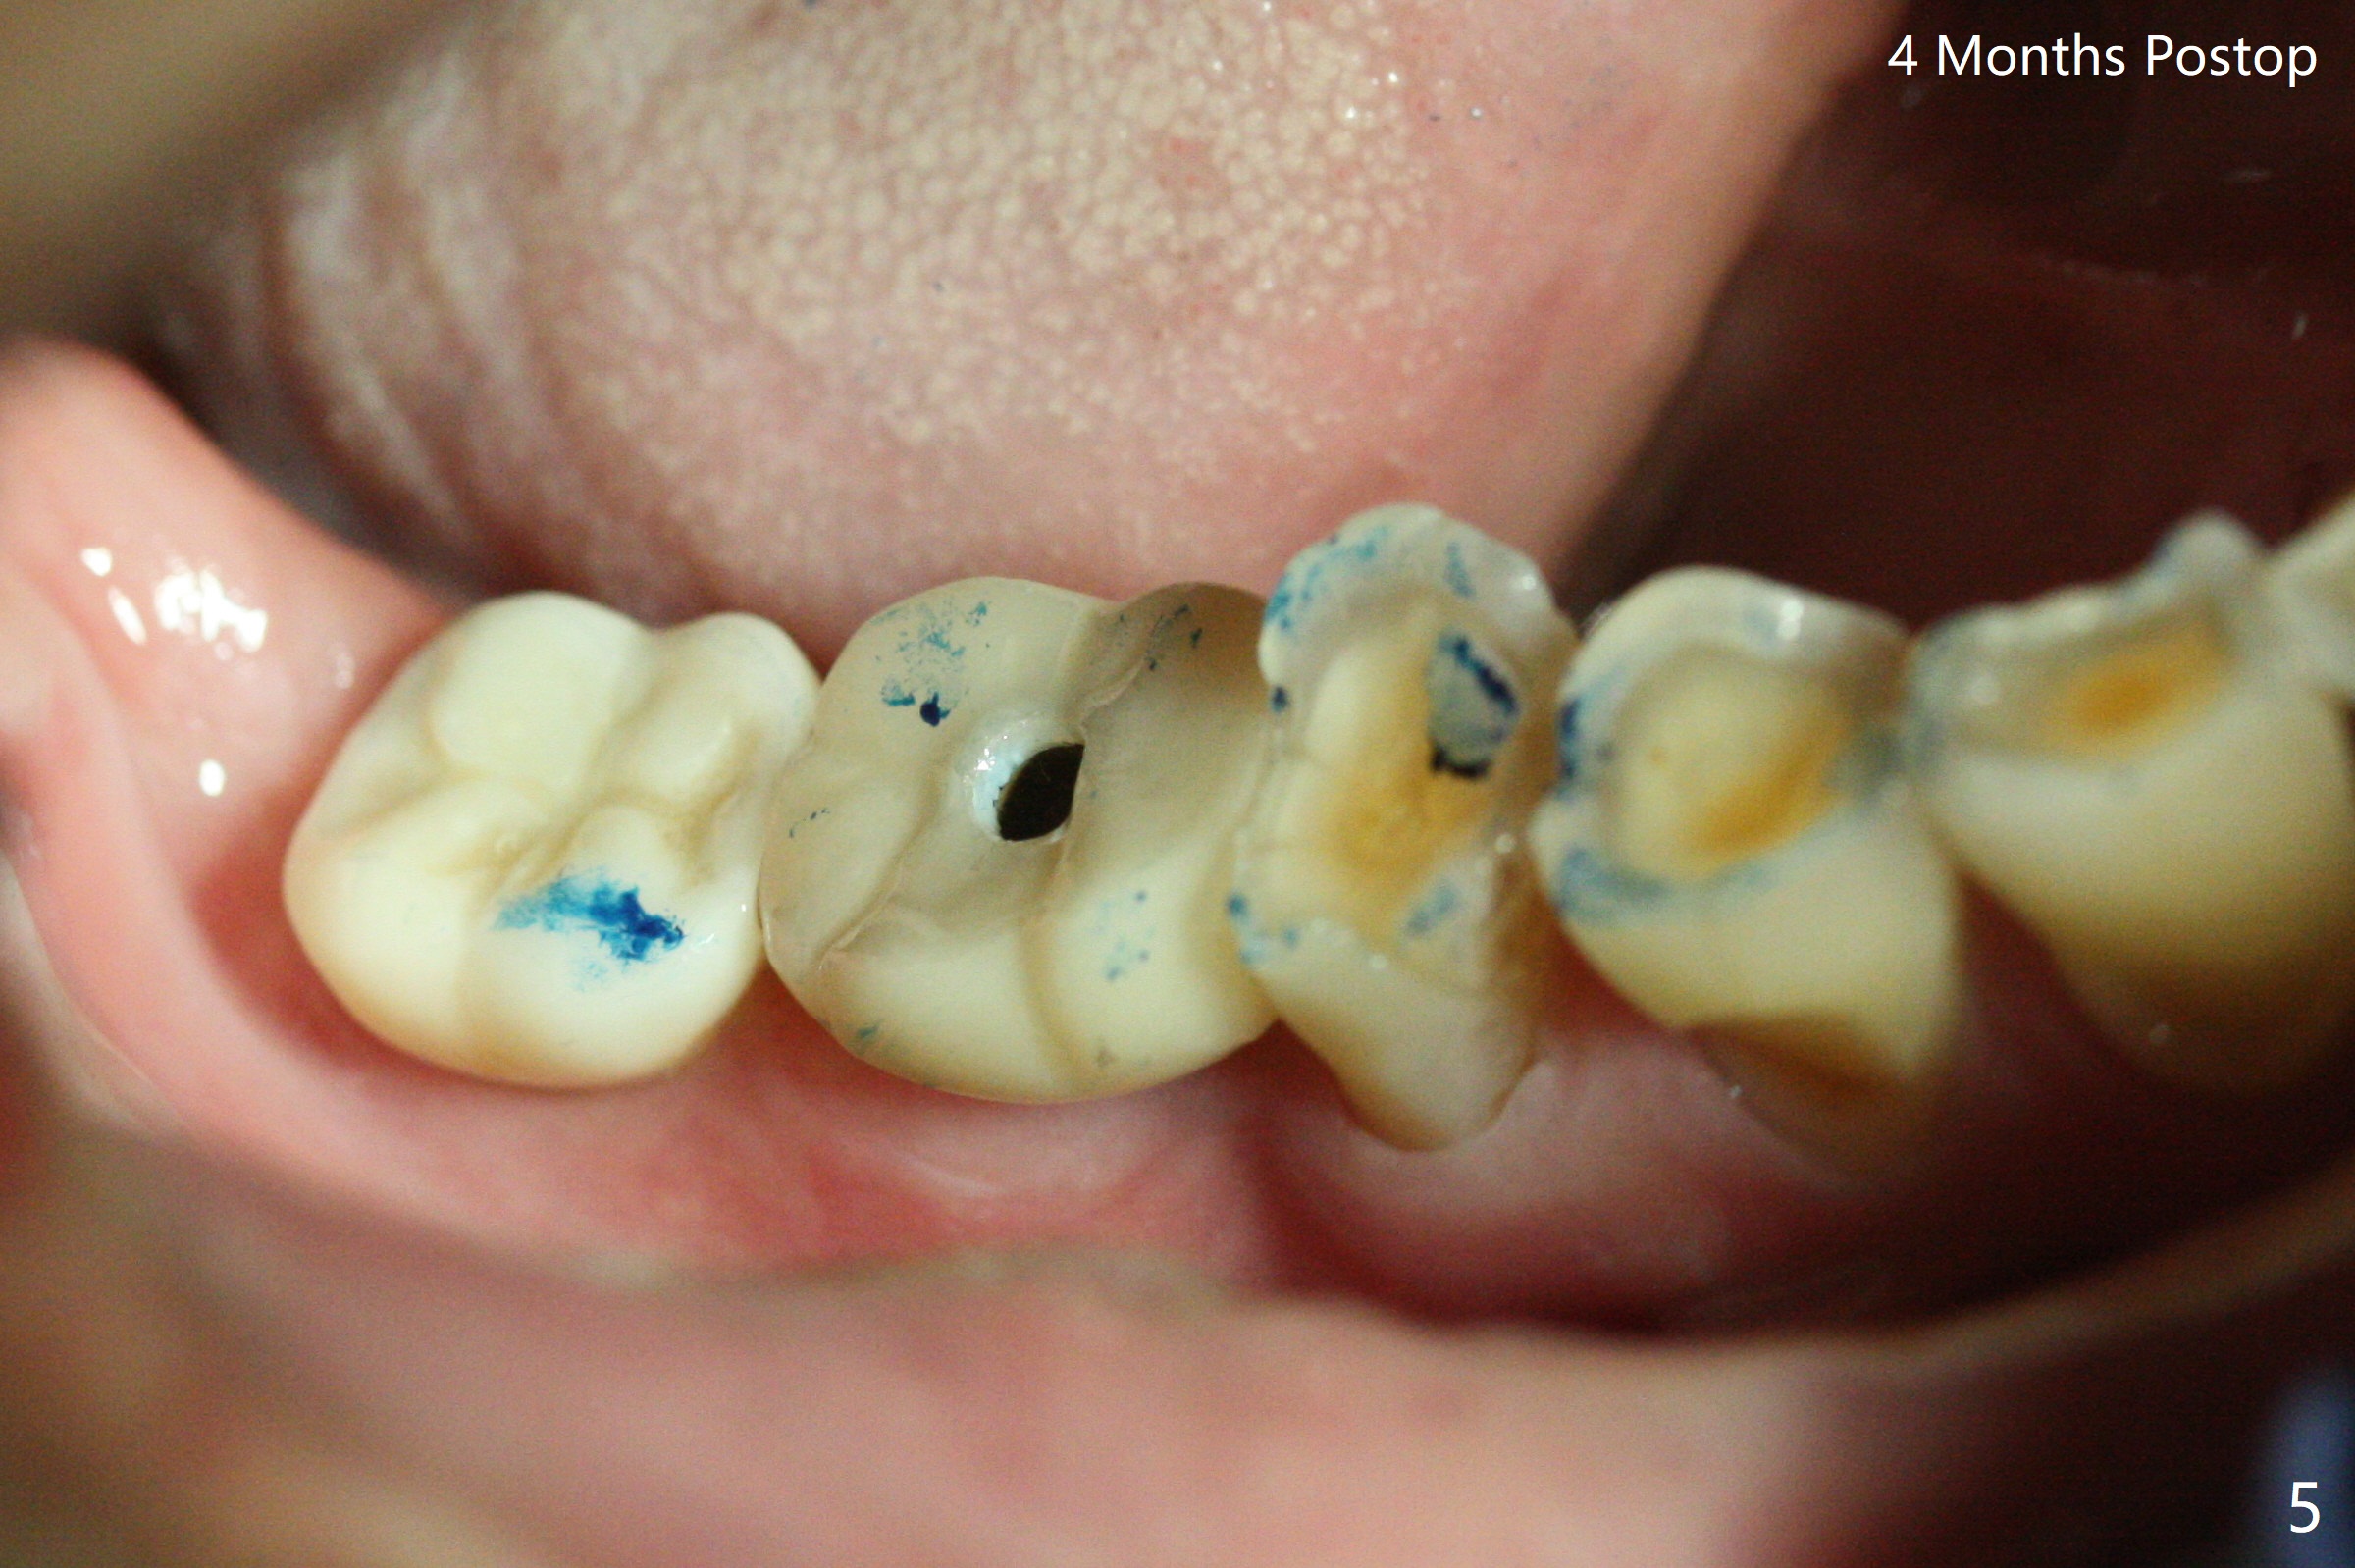

M

Vertical fracture of the mesial root of the tooth #30 after RCT is associated with bone loss (Fig.00 *). When the mesial portion of the mesial root (M', loose one) is exfoliated, the bone loss resolves (Fig.0). To reduce heat-induced bone necrosis at #19, osteotomy is conducted slowly with copious irrigation with cold saline. Bone density is felt while a 5x10 mm implant is being placed after using cortical tap to the 2nd line of the implant driver. The implant needs to be reverse torqued several times before reaching its final depth (Fig.1 (~50 Ncm)). Since the residual roots are superficially positioned, the immediate implant looks as a delayed one. Although the implant is placed mesial to the septum clinically, its position in X-ray seems to be normal. Because of severe wear and lack of vertical height, a 6.8x5 mm healing abutment is placed. Retention of bone graft (Fig.1 *) is maintained by spreading setting acrylic into the edentulous undercut areas (Fig.2 *). The so called "acrylic dressing" remains in place 3 weeks postop (Fig.8). When it is removed with the healing abutment, the wound heals (Fig.3). Note the limited vertical height. The bone graft placed in the distal socket appears to have been converted to the native bone 3.5 months postop (Fig.4). To reduce severe wear of the natural teeth, the occlusion of the new crown is not heavily decreased (Fig.5). It should be alright considering favorable crown/implant ratio (Fig.6). There is no bone loss 5 months post cementation, although the abutment screw is just retightened (Fig.7). In spite of poor trajectory associated with #18 (Fig.8) and 31 (Fig.7) Bicon implants, the abutments have not been dislodged. For the bruxer, the next implant at #19 with distal root fracture (Fig.8 ^) should be Bicon. The patient complains of food impaction nearly 1 year post cementation. The mesial and distal contacts of #30 crowns are light. When the abutment/crown is removed, there is implant well contamination (food debris). It appears that the previous abutment (5.7x4(2) mm, Fig.6,7) is incompletely seated. When a smaller abutment is placed and torqued at 30 Ncm, it is seated fully (Fig.9 (<: no gap)). New impression is taken. The distal gingival embrasure is larger than the mesial one because of the higher distal crest (Fig.6,7). If there is food impaction distal to the new crown, the distal crestal bone should be removed with lab closure of the embrasure.